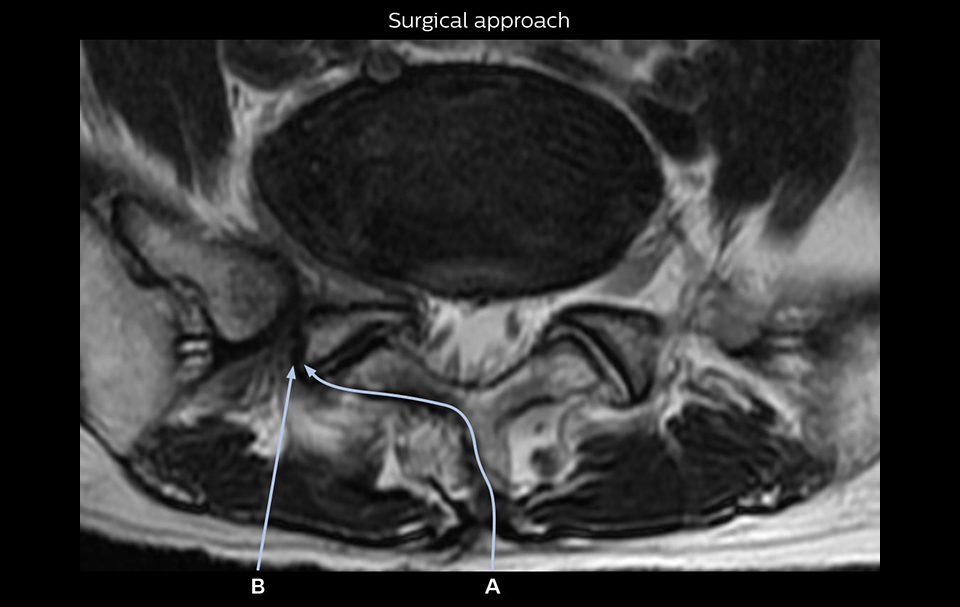

“Recently, the two surgical methods extreme and oblique lateral interbody fusion (XLIF and OLIF) have become mainstream for minimally invasive treatment of lumbar spinal canal stenosis and intervertebral foramen stenosis. With these surgical techniques, the spine is approached from the flank, and prior knowledge of the exact anatomy of the lumbosacral plexus would be extremely helpful. To that end, high slice resolution (less than 1 mm acquisition) that enables sharper sagittal MPR images will be needed.”

“For both brachial and lumbar plexus, we are currently using a 230 mm FOV and voxels of about 1 x 1 x 2 mm acquired (1 x 1 x 1 mm reconstructed). This provides us a good representation of the nerves, even though this FOV is relatively small. Regarding the inplane resolution, we hope to be able to bring that down to 0.7 mm, similar to our typical 2D multislice T2W images,” says Tanji.

The addition of the nerve-selective NerveVIEW sequence to its spine MRI protocol has given NFMC competitive advantages, according to Tanji. “Since we started including NerveVIEW routinely, the demand for lumbar spine MRI examinations has increased, especially for pre-surgical planning purposes and for patients with chronic lower extremity symptoms,” he says. “Moreover, because no other hospitals in our region are doing nerve plexus imaging yet, we often receive referrals for MR neurography studies from other hospitals even if they have an MRI scanner. Some requests come from as far as 100 km away. NerveVIEW definitely provides us a competitive advantage.” “Based on our experience, we can certainly recommend NerveVIEW to other centers,” Dr. Yabuki adds. “The sequence opens up many possibilities to facilitate the diagnosis of lower extremity pain and to inform our decision-making regarding therapy and surgery.”